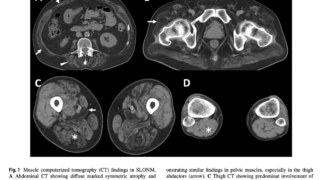

本邦からの報告では40%近くは肺野に病変を認めず、約60%に骨・関節病変、半数にリンパ節病変を認めている。

全身の臓器に感染しうるが、リンパ節48-82%、肺61-64%、骨・関節58-61%、皮膚26-70%への感染が多い。